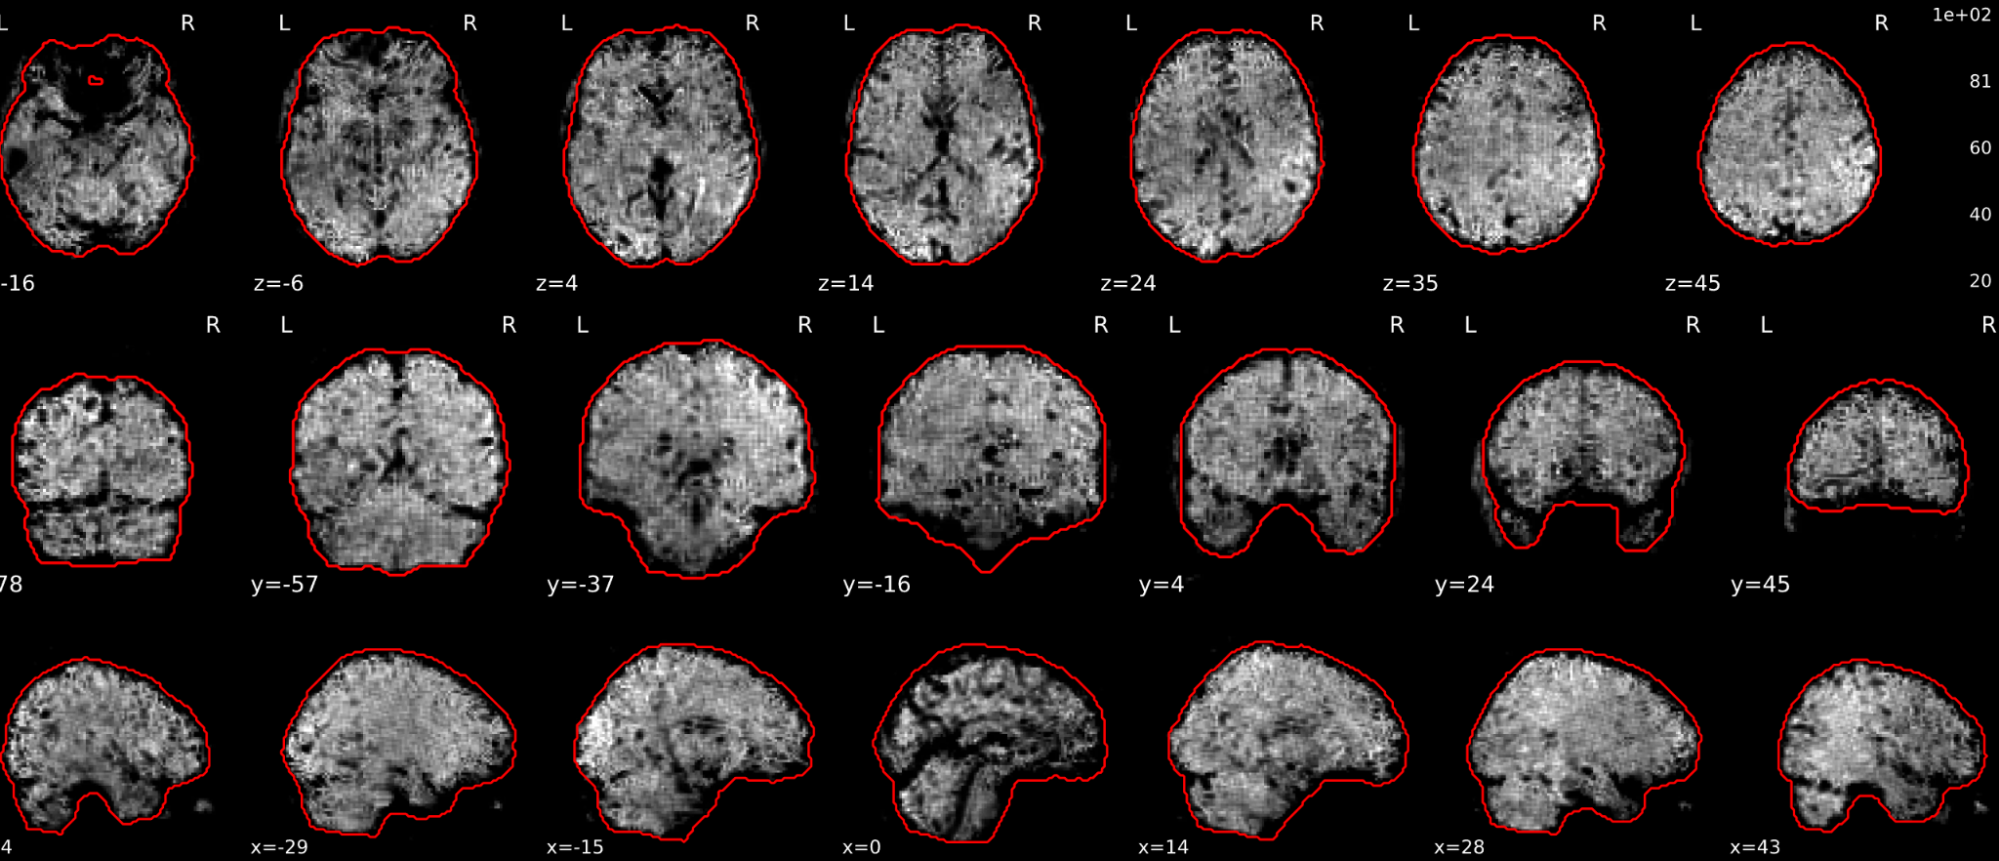

EPI tSNR

In the signal to noise ratio images of the resting state image the desired signal is compared to the amount of background noise. It is important to check all the views (sagittal, coronal, axial) because some artefacts (e.g., stripes) may be evident only in one particular view.

Example of a good subject

- Signal to noise is symmetrically distributed and there is no signal distortion

Example of a bad subject

- Asymmetry

- Potential signal distortion (might represent an artefact)

- Signal drop-out

- Stripes artefact

Clear large artefact (e.g., zebra stripes in example 1) are worth the exclusion of the subject. If you are unsure, check the other quality metrics for that subject to decide whether they should be excluded.

Summary

| good | bad |

|---|---|

| Symmetrical distribution of noise and signal | Asymmetry |

| No disruptions of the signal (no “black patches”) |

Potential signal disruptions (could be related to artefacts) |

| No stripes (sign of high motion) |

Signal drop |

| Stripe artefacts (“zebra” stripes due to motion) |